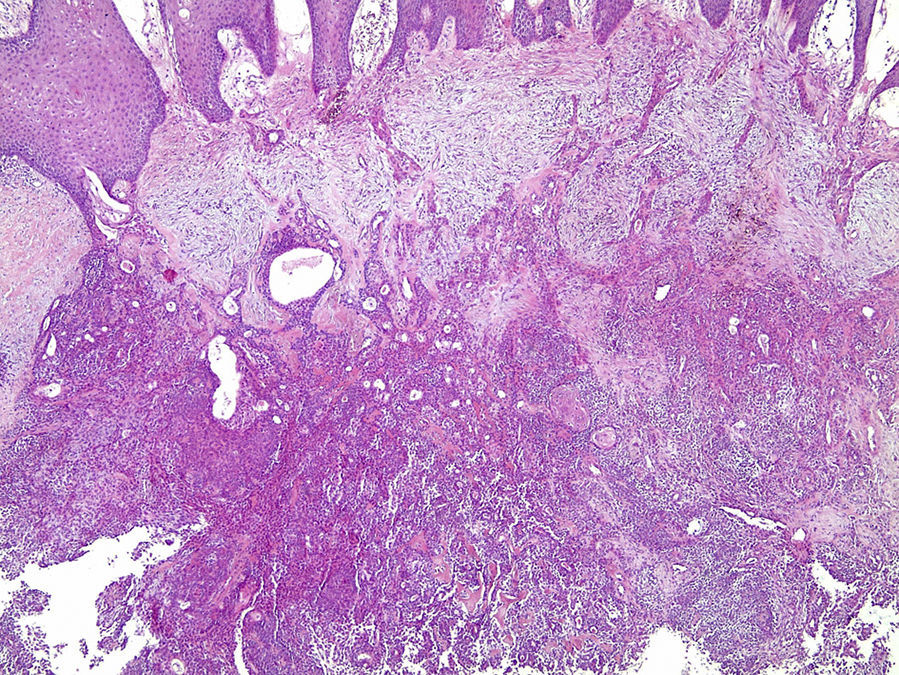

Os cortes histológicos, corados em hematoxilina e eosina, mostraram neoplasia de glândula salivar benigna, constituída por células epiteliais e mioepiteliais, parcialmente envolvida por fina cápsula de tecido conjuntivo fibroso (fig. 5). As células epiteliais encontravam‐se formando lençóis ou estruturas ductiformes, enquanto as células mioepiteliais formavam áreas mixoides, hialinas (fig. 6) ou exibiam aspecto plasmocitoide (fig. 7). O diagnóstico de adenoma pleomórfico foi confirmado. Paciente queixou‐se de desconforto no palato quando se alimentava, durante as 2 primeiras semanas após cirurgia. O paciente está sendo acompanhado clinicamente e, 2 anos após a cirurgia, não apresenta sinais de recidiva da lesão (fig. 8).

Os cortes histológicos mostraram neoplasia benigna de glândula salivar, envolvida por cápsula de tecido conjuntivo fibroso (fig. 14). O parênquima neoplásico é constituído por células epiteliais dispostas em lençóis e estruturas ductiformes, além de células mioepiteliais formando áreas mixoides e hialinas (fig. 15) ou apresentando‐se com morfologia plasmocitoide (fig. 16). O diagnóstico de adenoma pleomórfico foi confirmado. A paciente relatou ausência de dor no pós‐operatório e manteve utilização da placa de acrílico por 4 semanas. A paciente encontra‐se em acompanhamento e o exame clínico após 2 anos da remoção cirúrgica mostrou adequada cicatrização e ausência de sinais de recidiva da lesão (fig. 17).